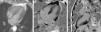

Cardiac magnetic resonance imaging. Cine true fast imaging with steady-state free precession in 4-chamber at end-systole (A) shows normal contractility of the left ventricular apex with complete resolution of apical ballooning; 4-chamber (B) and 2-chamber (C) delayed post-contrast imaging shows no abnormal myocardial enhancement.